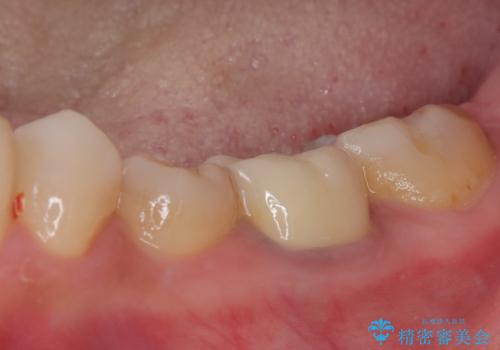

状況次第では抜歯が必要となり、その際にはインプラント治療を行うことを了承いただいた上で、破折していない場合には根管治療を行うこととしました。

土台の材料を外して顕微鏡下で確認したところ、歯根にまで及ぶ破折が認められたため、インプラント治療を行うこととしました。